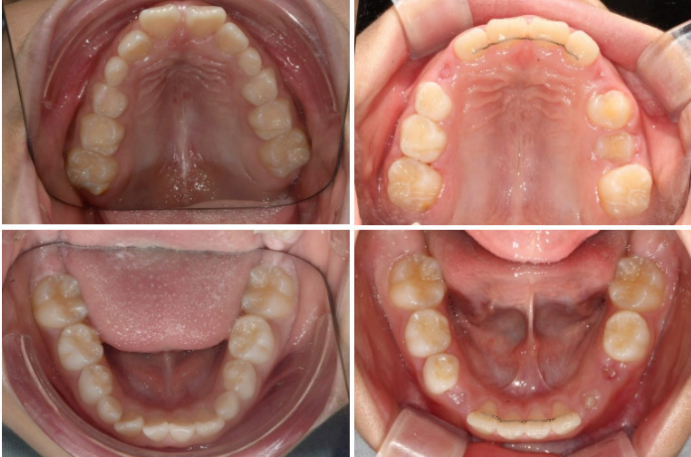

입천장은 좁고 앞니는 삐뚤합니다.

23.09

좁았던 입천장 악궁이 넓어졌고 앞니 배열이 가지런해졌습니다.

클린체크 치료계획상 25단계 장치에서 기대되는 치열이고 치료경과가 좋아서 실제 입안 상태도 비슷합니다.

24.01

송곳니 날 자리를 충분히 마련해주었습니다.